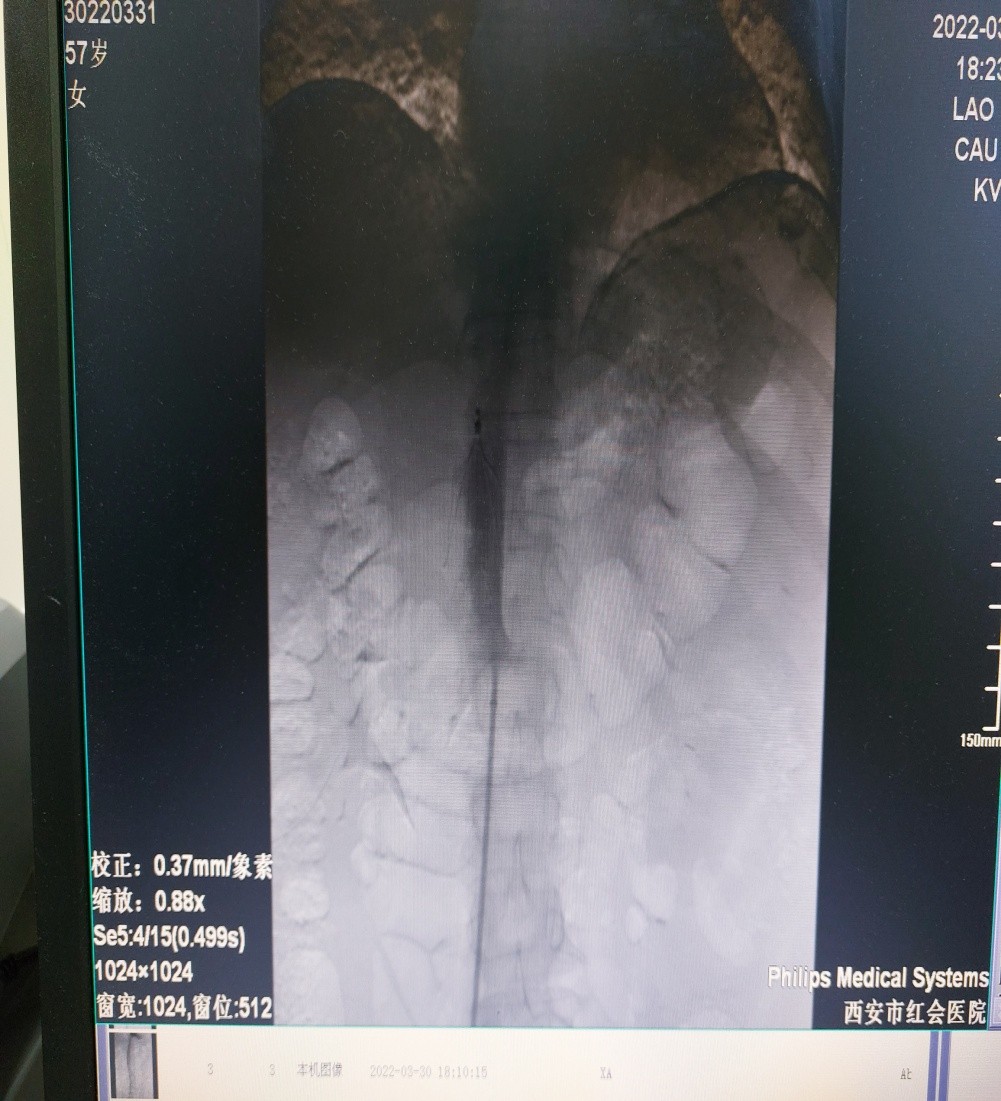

周围血管科袁会军主任查看病人后立即收治入院,并紧急进行了下腔静脉滤器植入手术,术中造影可见下腔静脉血栓已齐深静脉开口水平,于是将滤器植入定位在肾静脉开口之上。目前,该患者病情稳定。